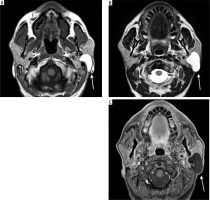

Case 4: Tongue haemangioma

A 25-year-old female presented with a bluish nodule on the ventral aspect of the tongue. On MRI, the lesion appears well defined and isointense to mildly hypointense compared to the surrounding muscle on the T1-weighted image (Figure 7A). It demonstrates a classic hyperintense appearance on the T2-weighted sequence, a hallmark feature of fluid rich or vascular lesions (Figure 7B). Post-contrast, T1-weighted, fat-saturated (T1 C+ Fat sat) imaging shows strong enhancement of the lesion, confirming its vascular nature (Figure 7C).

Figure 7

Axial section of MRI of tongue haemangioma: A) T1-weighted, B) T2-weighted, C) T1 C+ Fat sat. These findings are essential for distinguishing haemangioma from other tongue masses and for assessing lesion extent and vascularity, which is critical for safe surgical excision and functional preservation [Courtesy: Radiopaedia. DOI: https://doi.org/10.53347/rID-84386, rID: 84386]